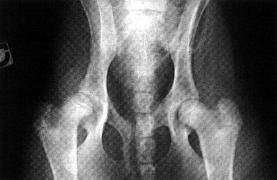

- Le jugement repose sur la recollection des différents critères pour aboutir au classement des hanches tel qu'il est appliqué actuellement

* A = AUCUN SIGNE DE DCF : Bonne congruence articulaire et angle de NO supérieur ou égal à 105°.

* B = ETAT SENSIBLEMENT NORMAL . Bonne congruence articulaire et angle de NO compris entre 100 et 105° ou congruence imparfaite et angle de NO supérieur ou égal à 105°.

* C = DCF LEGERE Congruence articulaire imparfaite et angle de NO compris entre 100 et 105°.

* D = DCF MOYENNE : Mauvaise congruence articulaire, souvent pincement de l'interligne articulaire en région crânio-acétabulaire, angle de NO compris entre 90 et 100°, éventuellement signes d'arthrose.

* E = DCF SEVERE

Sub-luxation ou luxation, angle de NO inférieur à 90°, arthrose fréquente, et souvent sévère.

* Bascule du bassin

C'est un défaut fréquent et extrêmement gênant des clichés radiographiques

- Comment le voit-on ? La bascule du bassin se diagnostique grâce à l'image des ailes de l'ilium et des foramen obturés.

Du côté de la bascule, l'aile de l'ilium apparaît plus large alors que le foramen obturé est plus petit que son homologue du côté opposé .

- Quelles sont les conséquences de la rotation ? Du côté de la rotation, la profondeur de l'acétabulum paraît moindre et la couverture acétabulaire moins bonne. Du point de vue du jugement, la

hanche du côté de la rotation est "pénalisée", celle de l'autre côté est "favorisée". Lorsqu'il y a bascule du bassin, la lecture est plus difficile voire impossible. En cap de doute, il faut refaire la radiographie.